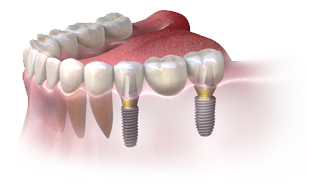

Punte dentară fixată pe implanturi: Dacă există mai mulți dinți lipsă într-o zonă, o punte dentară pe implanturi este alegerea potrivită. Aceasta permite înlocuirea confortabilă a unui sau mai multor dinți lipsă, conectând protezele între ele prin intermediul implanturilor.

ÎNAINTE

DUPĂ